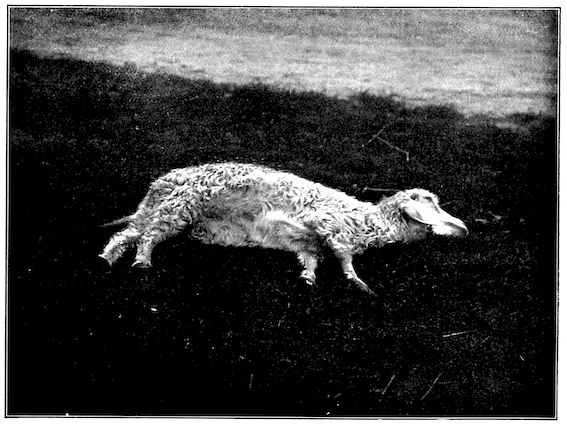

Fig. 3.—Pig suffering from osseous cachexia (fourth stage).

Such shocks would be of no importance to a healthy animal, but to one suffering from osseous cachexia, any violence, or even the slightest muscular effort may be followed by fracture of the gravest character, involving even the vertebral column. In cows the pelvis, femur, and tibia are most frequently injured.

In horses, particularly in riding horses, fractures are commonest in the region of the forearm, cannon bone, and anterior phalanges. So extremely fragile are the bones at this stage that the horse represented herewith broke twelve ribs at one time by simply falling on its side. It is interesting to note that such fractures are never accompanied by any extensive bleeding. They have little tendency to repair, no real callus formation occurs, and on post-mortem examination one often finds the ends unconnected by temporary callus, worn, and rounded by reciprocal friction.

At this stage but under other circumstances, the animals show great reluctance to rise, remaining down for twelve to twenty-four hours without shifting their position. If forced to get up, they stand as though fixed in one position, the respiration and circulation become rapid, and they soon grow tired and fall.

114. The fourth phase, or period of osteomalacia, i.e. softening of the bones, is also the last. It is rarely seen in large animals like horses and oxen, because accidents so often accompany the preceding stages and necessitate slaughter; but it is common in goats and pigs.